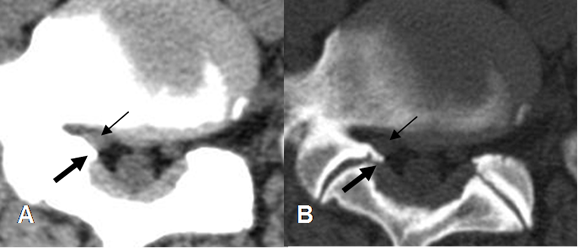

Fig 64. Canal estrecho lateral.

A: TAC axial en ventana de tejido y B: TAC axial en ventana de hueso. Estenosis del receso lateral, por hipertrofia de articulaciones intervertebrales y presencia de osteofito. (Flecha gruesa). Disminución de la grasa que rodea la raíz nerviosa. (Flecha delgada).